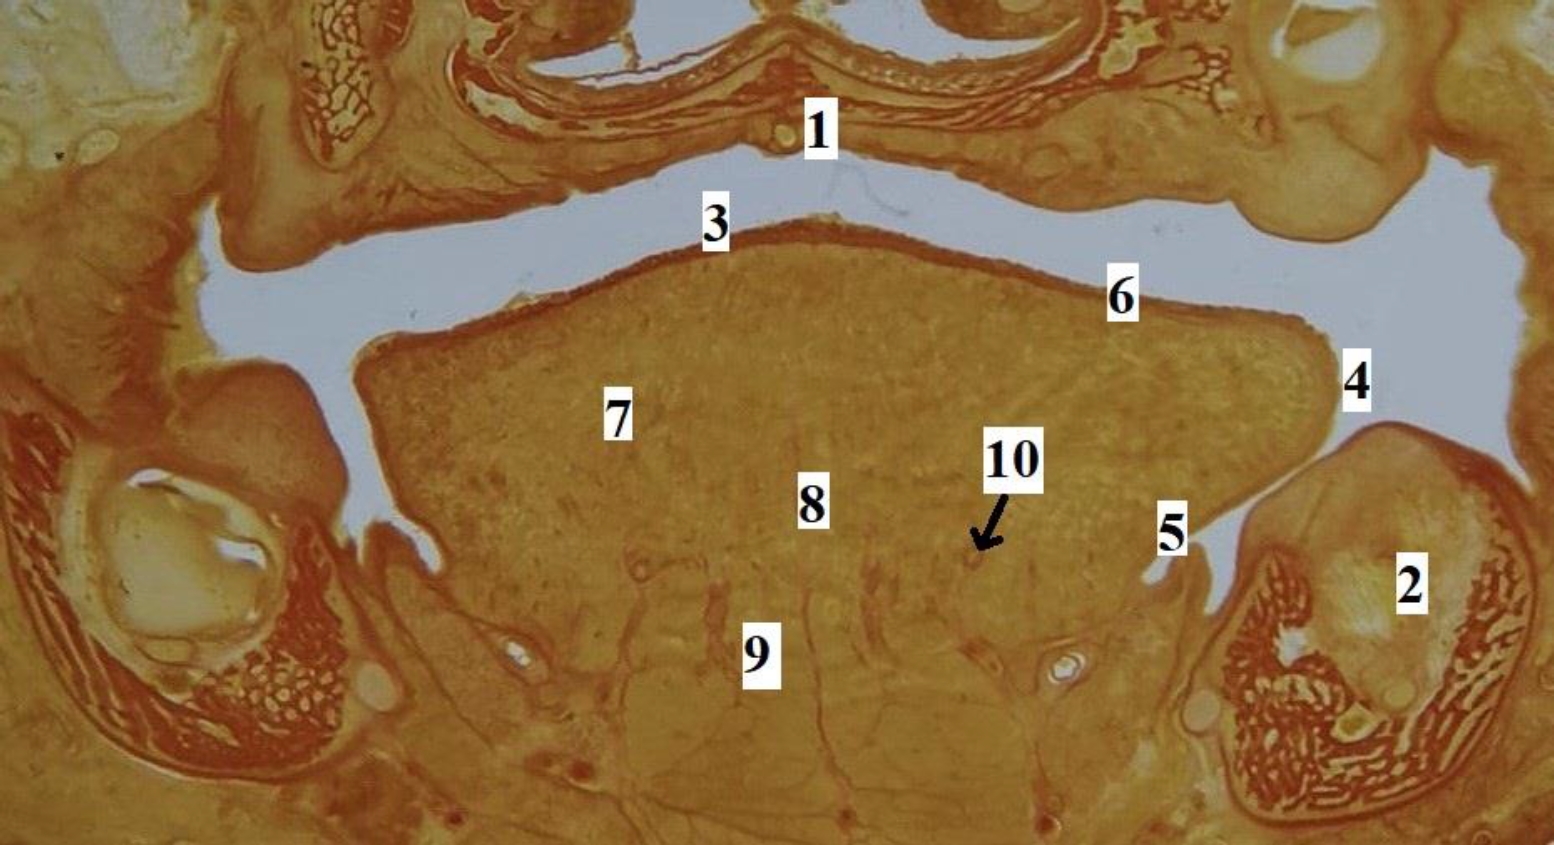

Язык человека в промежуточном плодном онтогенезе сформирован, макроскопически определяются все структурные элементы органа (рис. 2). На гистотопограммах визуализируется макромикроскопическая структура и микротопографические взаимоотношения мышц, сосудов, слизистой оболочки, стромального компонента языка (рис. 3). Линейные параметры языка, а также их описательная статистика представлены в табл. 2.

Рис. 2. Макропрепарат языка плода человека. Возраст – 17 недель, пол женский: 1 – слепое отверстие языка; 2 – пограничная борозда языка; 3 – спинка, предбороздовая часть тела языка; 4 – срединная борозда языка; 5 – край языка; 6 – верхушка языка; 7 – желобоватые сосочки языка; 8 – конусовидные, нитевидные, грибовидные сосочки языка

Рис. 3. Язык плода человека. Фронтальная гистотопограмма. Фото под микроскопом MicroOptix MX-1150, ок. ×10, об. 1. Возраст – 22 недели, пол мужской. Окраска по Ван – Гизону: 1 – твердое нёбо; 2 – нижняя челюсть; 3 – спинка языка; 4 – край языка; 5 – эпителий слизистой оболочки нижней поверхности языка; 6 – специализированный эпителий спинки языка; 7 – мышечные волокна поперечной мышцы языка; 8 – перегородка языка; 9 – мышечные волокна подбородочно-язычной мышцы; 10 – глубокая артерия языка